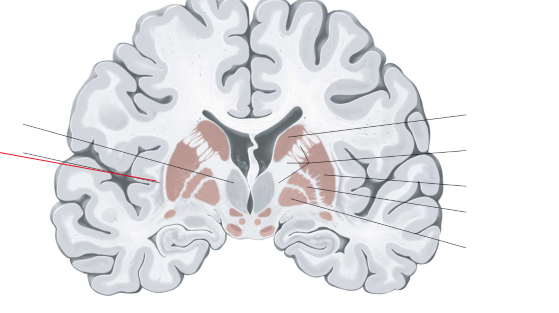

putamen

globus pallidus

capsula interna (corona radiata)

capsula externa

capsula extrema

hippocampus

amygdala

fornix